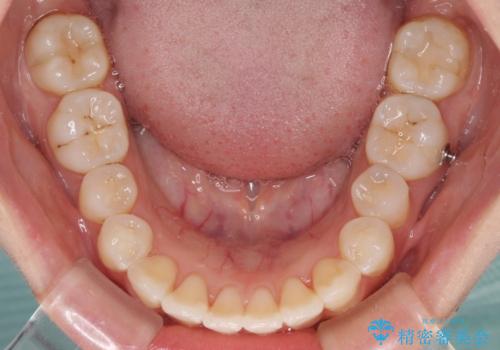

- 上下前歯のデコボコを気にして来院された患者様です。

インビザラインによる上下歯列の拡大と、IPR(歯と歯の間を削る)にるスペースの獲得により、前歯のデコボコを改善することとしました。

しっかりと装着時間を遵守してくださったので、思い通りの歯列に整えることができました。

結婚式前に終了させることができ、患者様には大変満足していただきました。